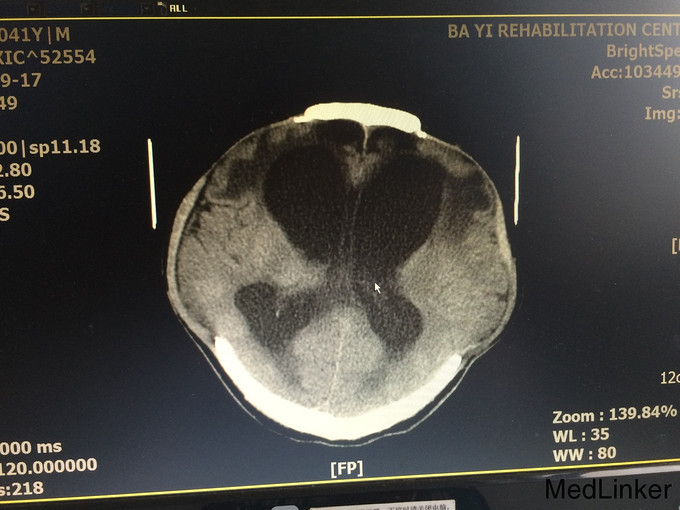

入院查体:气管切开,自带鼻饲管,生命体征稳定:脉搏 70次/分,血压121/71mmHg;Glasgow昏迷评分9分,最小意识状态;双侧颅骨缺如;四肢肌张力增高,肌力1-2级,左上肢肘关节活动受限。 辅查:血常规、肝肾功、凝血、电解质、血脂、血糖均正常;头颅MRI(2015.09.17)示:双侧额颞叶及右侧枕顶叶片状低密度影;交通性脑积水;双侧颞额顶骨部分缺如,相邻脑组织膨出,多系术后改变;头颅MRI(2015.09.28)示:与前面的片子比较,变化不大;

诊断:重型颅脑损伤 双侧额叶脑挫裂伤;双侧额颞顶部硬膜下血肿;脑疝形成;最小意识状态。 入院后治疗上积极给以神经营养、床旁康复治疗,高压氧治疗20天促醒;预防肺部感染;预防癫痫发作;

患者病情好转缓慢,2周前强直阵挛发作一次;影像资料提示颅内情况并未明显改善。请神经外科会诊后,建议作脑脊液侧脑室腹腔分流术。对于有脑积水的患者,不排除越早行脑脊液分流术,意识障碍恢复的时间就越短,效果就越好!另外,高压氧治疗方面,怎样发挥出最佳的治疗效果?